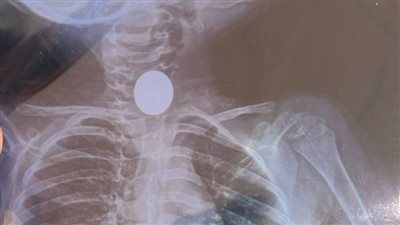

عملة معدنية كادت تودي بحياة طفلة وأطباء مناظير أبوكبير يتدخلون في الوقت المناسب

إنقاذ طفل من خطر الاختناق بعد ابتلاعه عملة معدنية بالشرقية

صحة الشرقية تنقذ حياة مرضى تعلقت عملة معدنية وعظمة وليمونة بمجرى الطعام